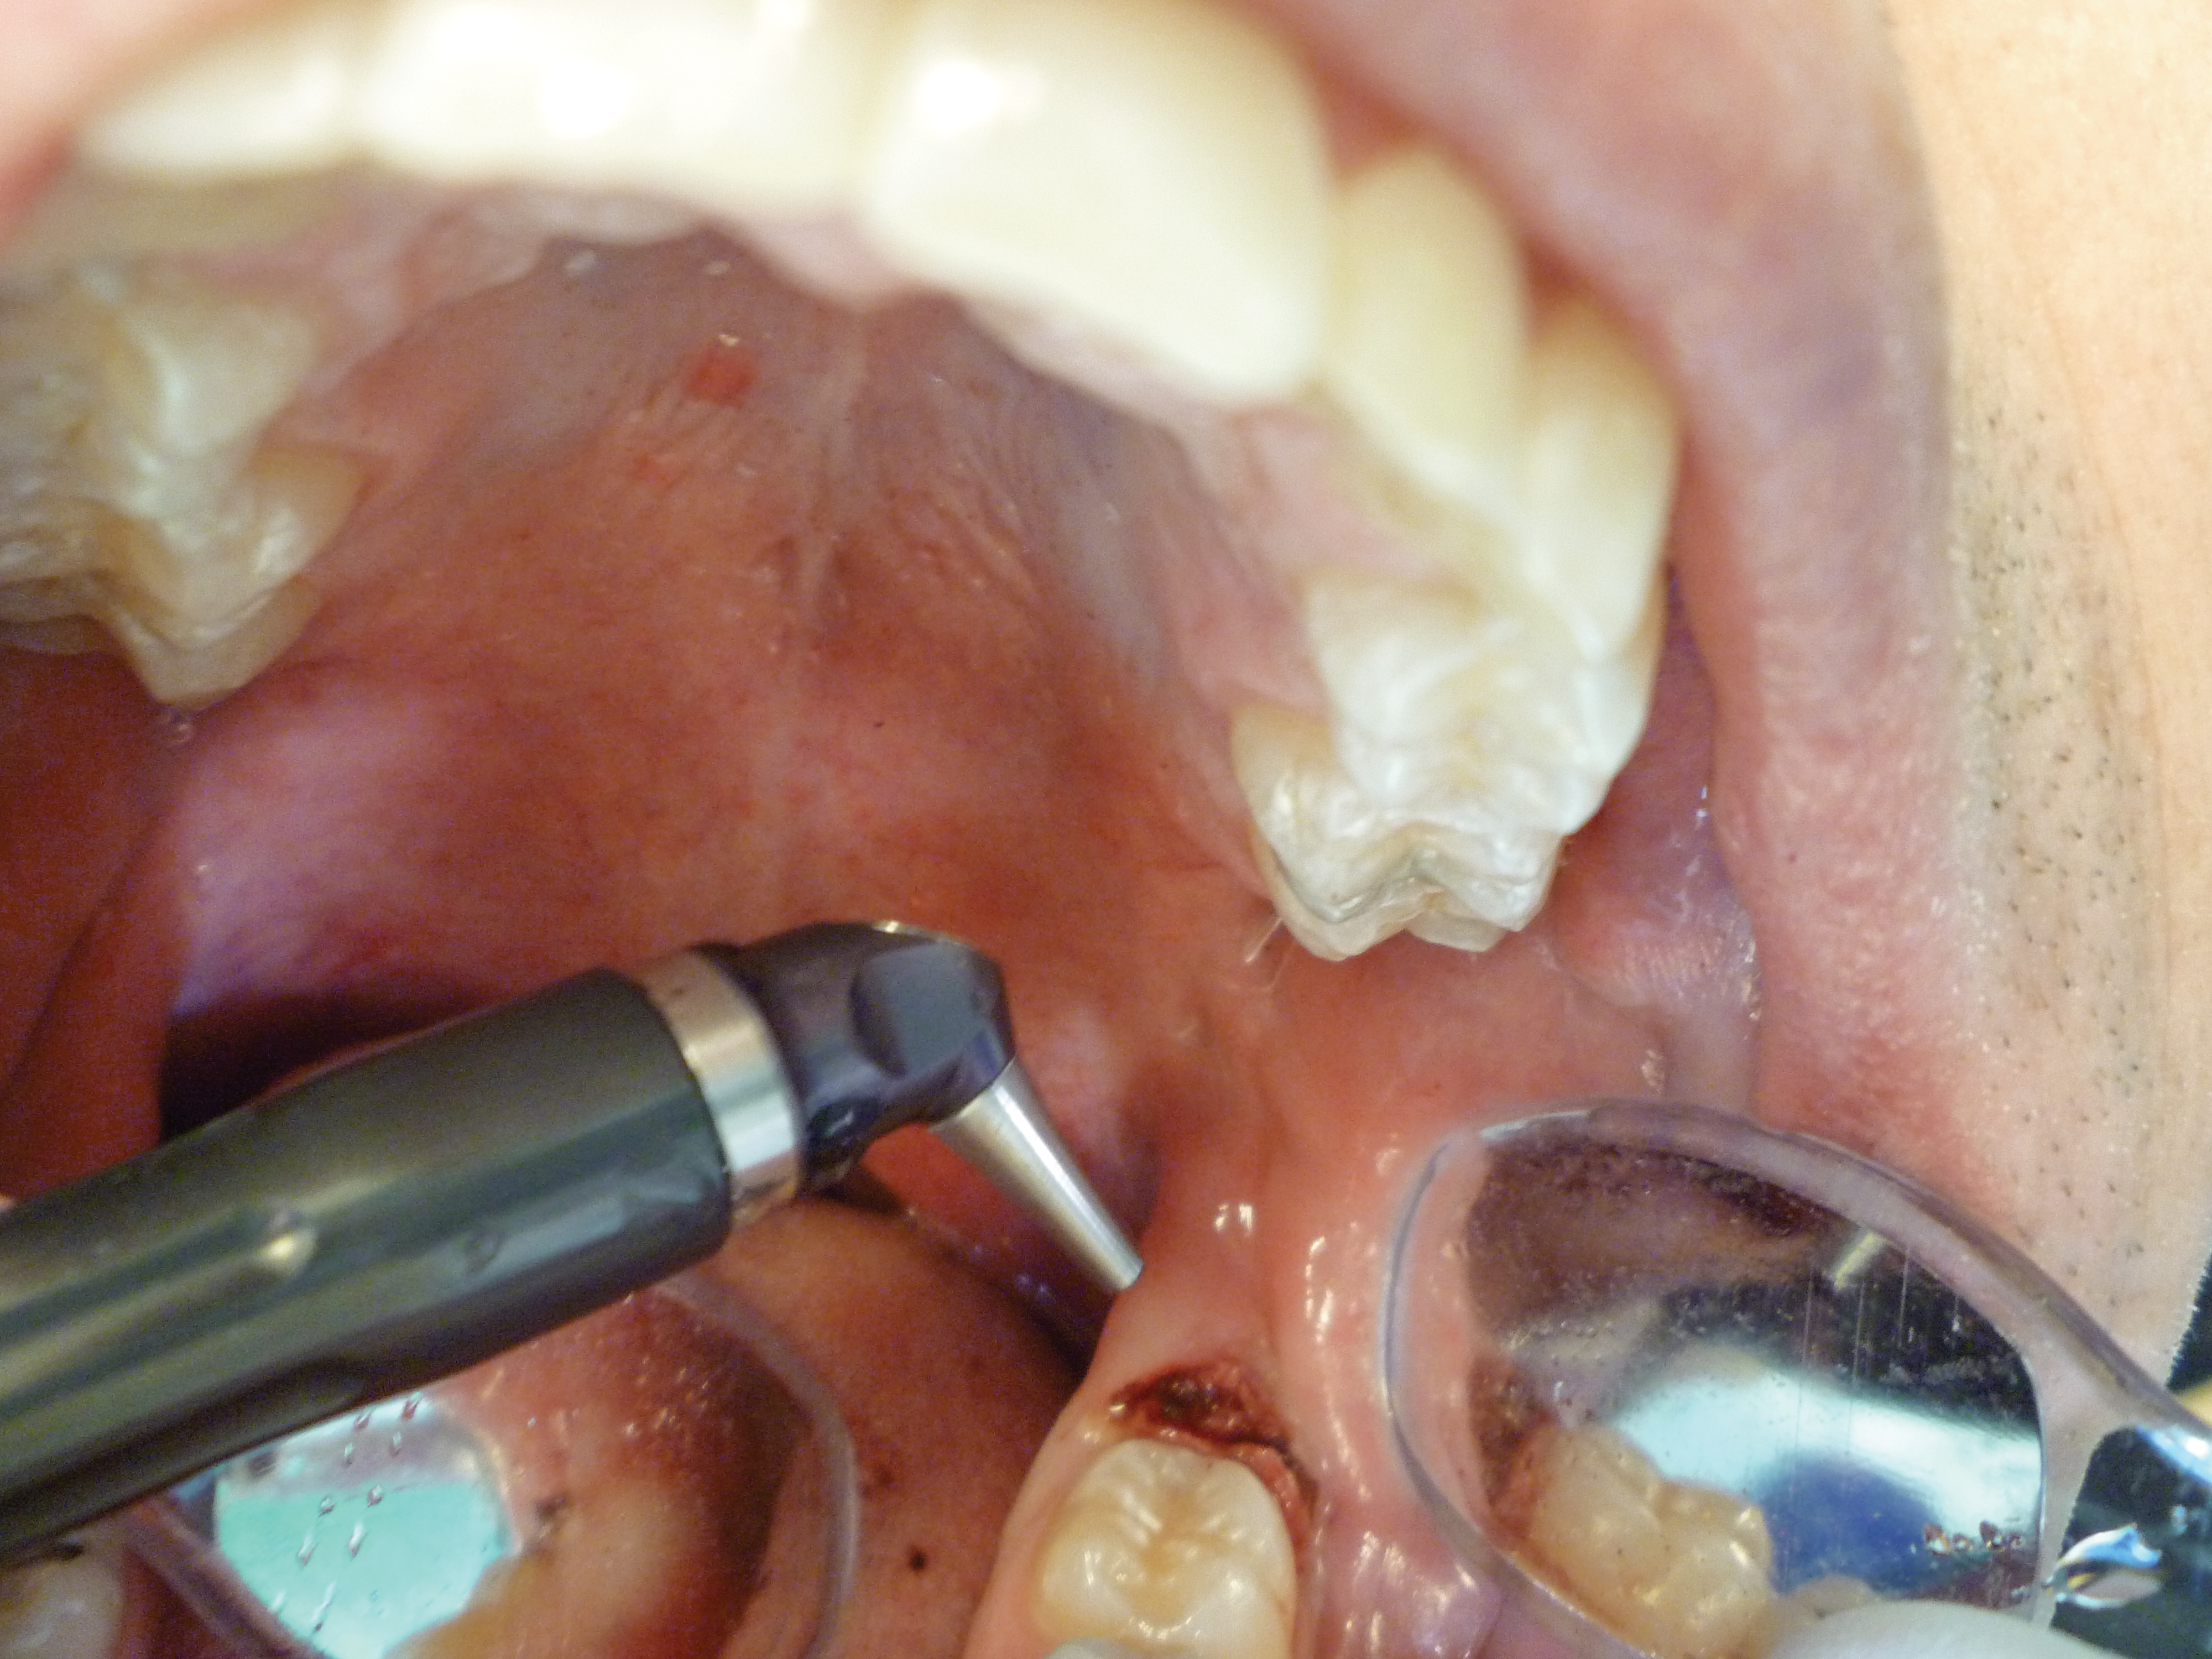

2. The angled handpiece of the CO2 laser was held perpendicular to the target lesion (Figure 4), and the ablation of the inflamed tissue began (Figure 5). The dental surgeon was careful to avoid contact between the laser beam and the tooth enamel. Note: In this case, the inflamed tissue was located distally from the involved molar. There was no direct contact of the beam with the tooth, as the surgeon was careful not to hit the enamel. However, if an operculum covers part of the tooth, an adaptive tool (for example, a wax spatula) needs to be inserted between the tissue and the tooth to prevent possible damage. For an inexperienced CO2 laser surgeon, it is important and highly recommended to always shield the tooth during the procedure.6

Fig 4. The angled handpiece of the CO2 laser was held perpendicular to the target lesion.

Figure 4

Fig 5. The ablation of the inflamed tissue began.

Figure 5